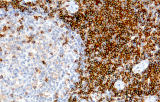

- Assegnazione del lignaggio & principali diagnosi differenziali: Fenotipizzazione cellule B vs cellule T (es. CD20 vs CD3), supportata da fattori di trascrizione nucleari delle cellule B come PAX5 quando i marcatori pan-B sono deboli/assenti.

- Linfoma follicolare: tipici pattern di co-espressione (es. CD10 con BCL2 aberrante).